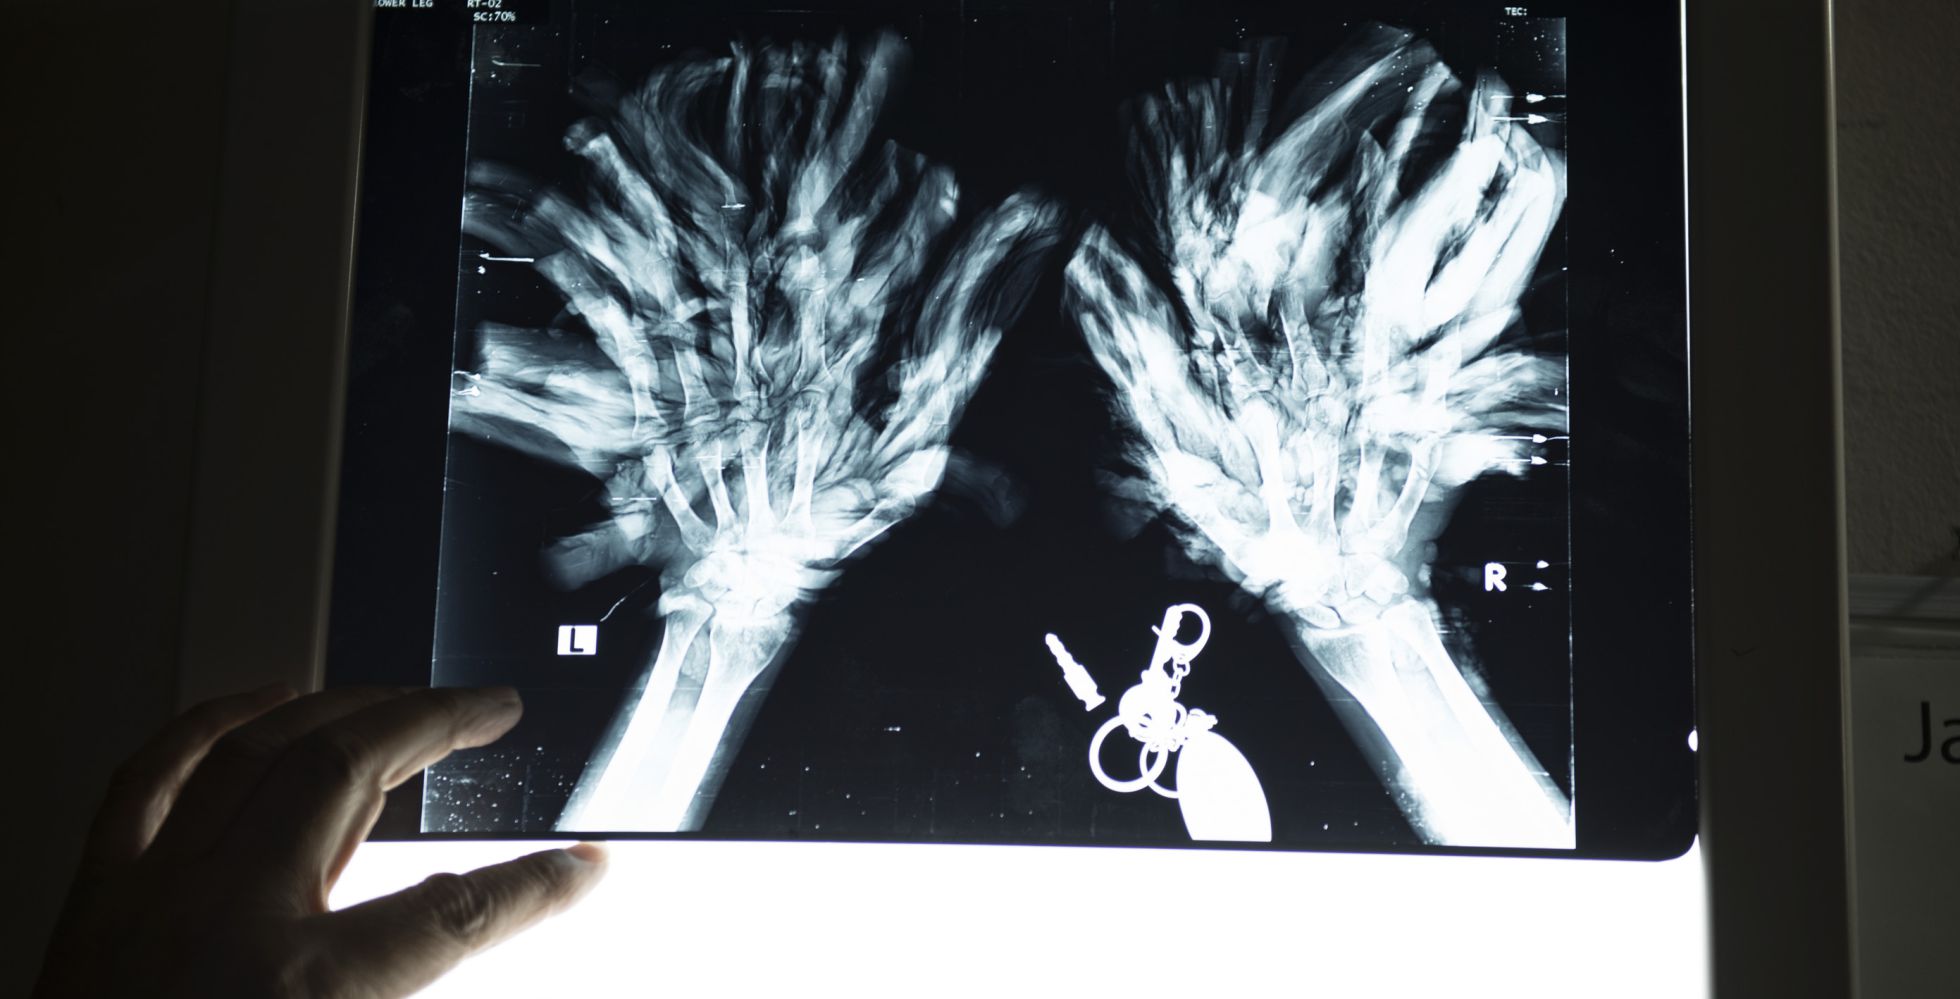

O conselho de nove médicos especialistas que o hospital criou para determinar o que fazer no caso dele também não está totalmente cheio de confiança. "O primeiro passo consiste em tentar liberar o polegar e o indicador de uma mão, que são responsáveis por 60% de todos os movimentos que fazemos. Também são os menos afetados e nos ajudarão a ver melhor qual é a situação e decidir quais passos devemos dar", diz o chefe do conselho, doutor Samanto Lal Sen, apontando para uma radiografia das mãos de Bajandar. "Não é tão fácil lidar com os dedos, e temos de ter muito cuidado para não danificá-los". Assim, as operações vão levar cerca de seis meses, aos quais se somarão outros vários meses de fisioterapia. "Ele só usou as mãos por dez anos, de forma que seus dedos estão completamente atrofiados".